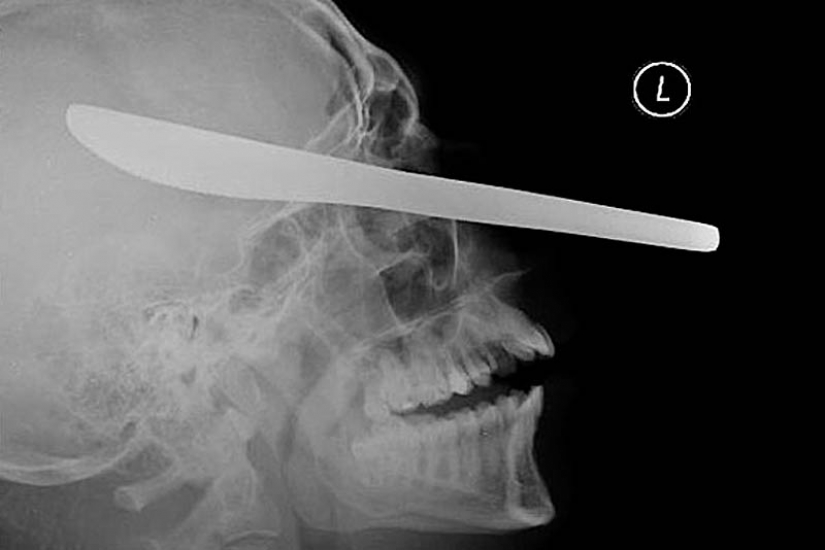

11. La lanza de la arpón, atrapados en la cabeza de un joven de 16 años de edad, niño de pesca.